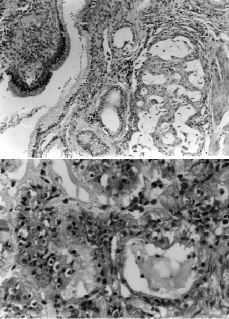

En los tumores considerados como sincrónicos (grupo A), el motivo de consulta más común fue la metrorragia postmenopáusica, salvo una paciente que aquejaba dolor en hipogastrio en la que se diagnosticó una masa anexial. Todas estas pacientes fueron sometidas a cirugía, siendo los hallazgos anatomopatológicos de adenocarcinoma endometrioide bien diferenciado tanto en el endometrio como en el ovario, salvo en un caso en el que se apreció un adenocarcinoma mixto endometrioide/mucinoso bien diferenciando en ambas localizaciones (Figs. 1 y 2). Tras la cirugía consideramos los cuatro casos como cáncer de endometrio estadío I y como cáncer de ovario estadío I (en las dos pacientes consideradas como ovario Ic la cápsula del tumor se había roto durante la cirugía). Tres pacientes recibieron radioterapia adyuvante después de la cirugía y una quimioterapia con regímenes de platino. El tiempo medio de seguimiento fue de 50 meses (rango: 68-28 meses). La paciente que presentaba un adenocarcinoma mixto mucinoso/endometrioide falleció a consecuencia de su enfermedad tras 65 meses de seguimiento, todas las demás enfermas se encuentran sanas en el momento actual.

Figura 1. Adenocarcinoma endometrioide bien diferenciado de útero con adenocarcinoma endometrioide bien diferenciado de ovario.

Figura 2. Adenocarcinoma bien diferenciado con patrón cribiforme y diferenciación mucosecretora y adenocarcinoma mixto endometrioide/mucinoso de ovario.